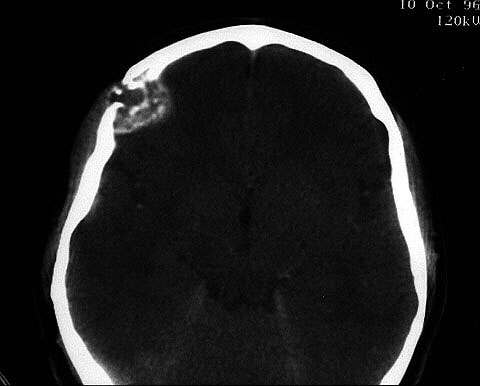

Fig. 2.Tras la administración intravenosa de contraste, la lesión presenta una captación de intensidad moderada y características irregulares. Los diagnósticos radiológicos fueron quiste óseo aneurismático, granuloma eosinífilo y meningioma. |